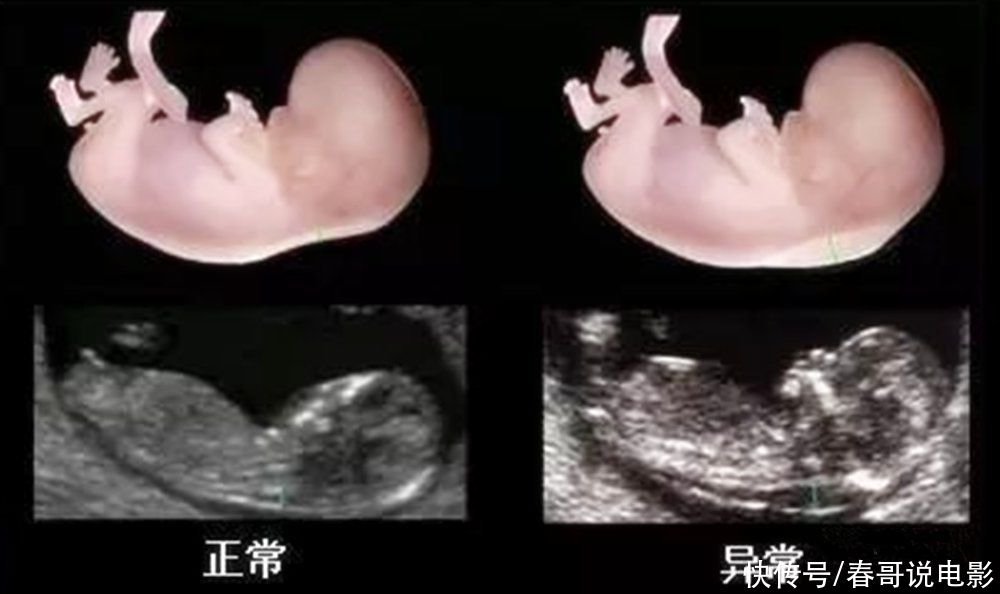

NT检查主要是通过测量胎儿颈部后方透明膜的厚度,来初步判断胎儿是否存在畸形和智力发育方面的欠缺,因此也是不能省略的。

3)大排畸检查

大排畸检查是个孕期所以孕检项目中,检查胎儿部位最全面的一项检查,除了看胎儿的外观,还会检查胎儿内部器官的发育情况。